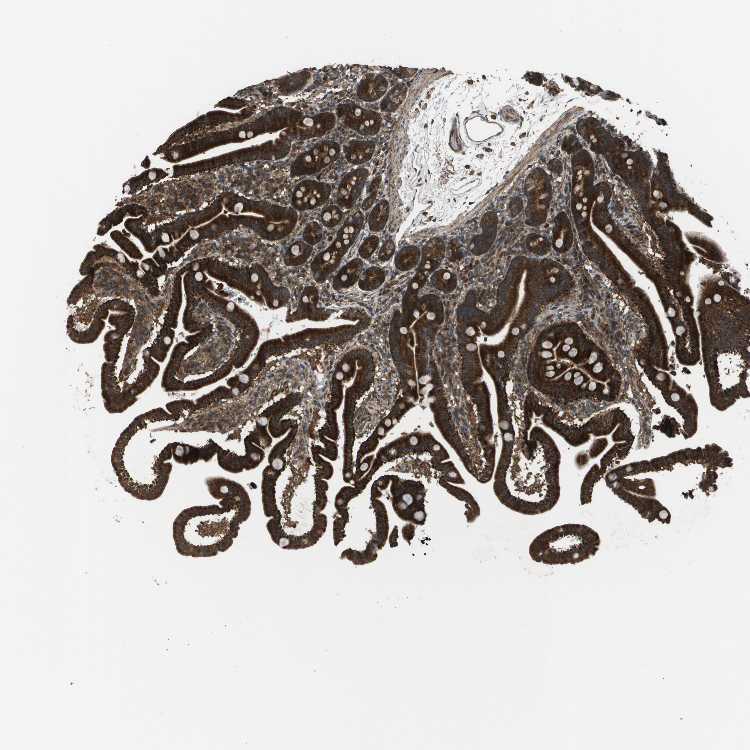

DUODENUM

Tissue proteome

Intestine